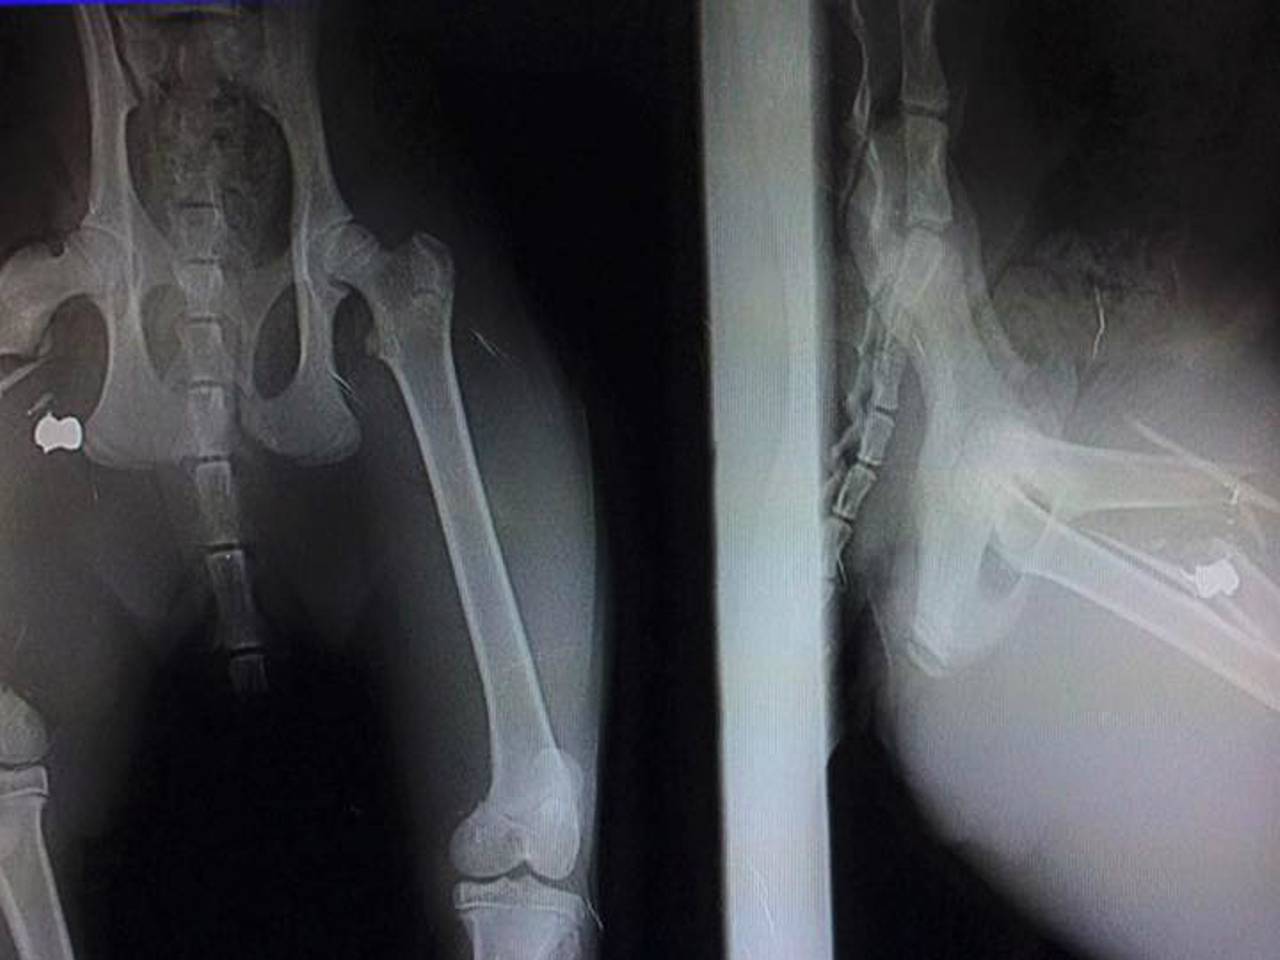

Kirsti Pol is verbijsterd. Zondagmorgen werd haar acht maanden oude kat Nikey beschoten in de Graafsewijk Noord in Den Bosch. Het bovenbeen van de kat is door de kogel verbrijzeld. “Hij heeft helse pijn”, schrijft Kirsti op Facebook.

Nikey wordt maandag aan zijn poot geopereerd. Er zijn minimaal twee operaties nodig om zijn poot te behouden. Na de operaties moet de kat drie maanden binnen blijven om te herstellen.